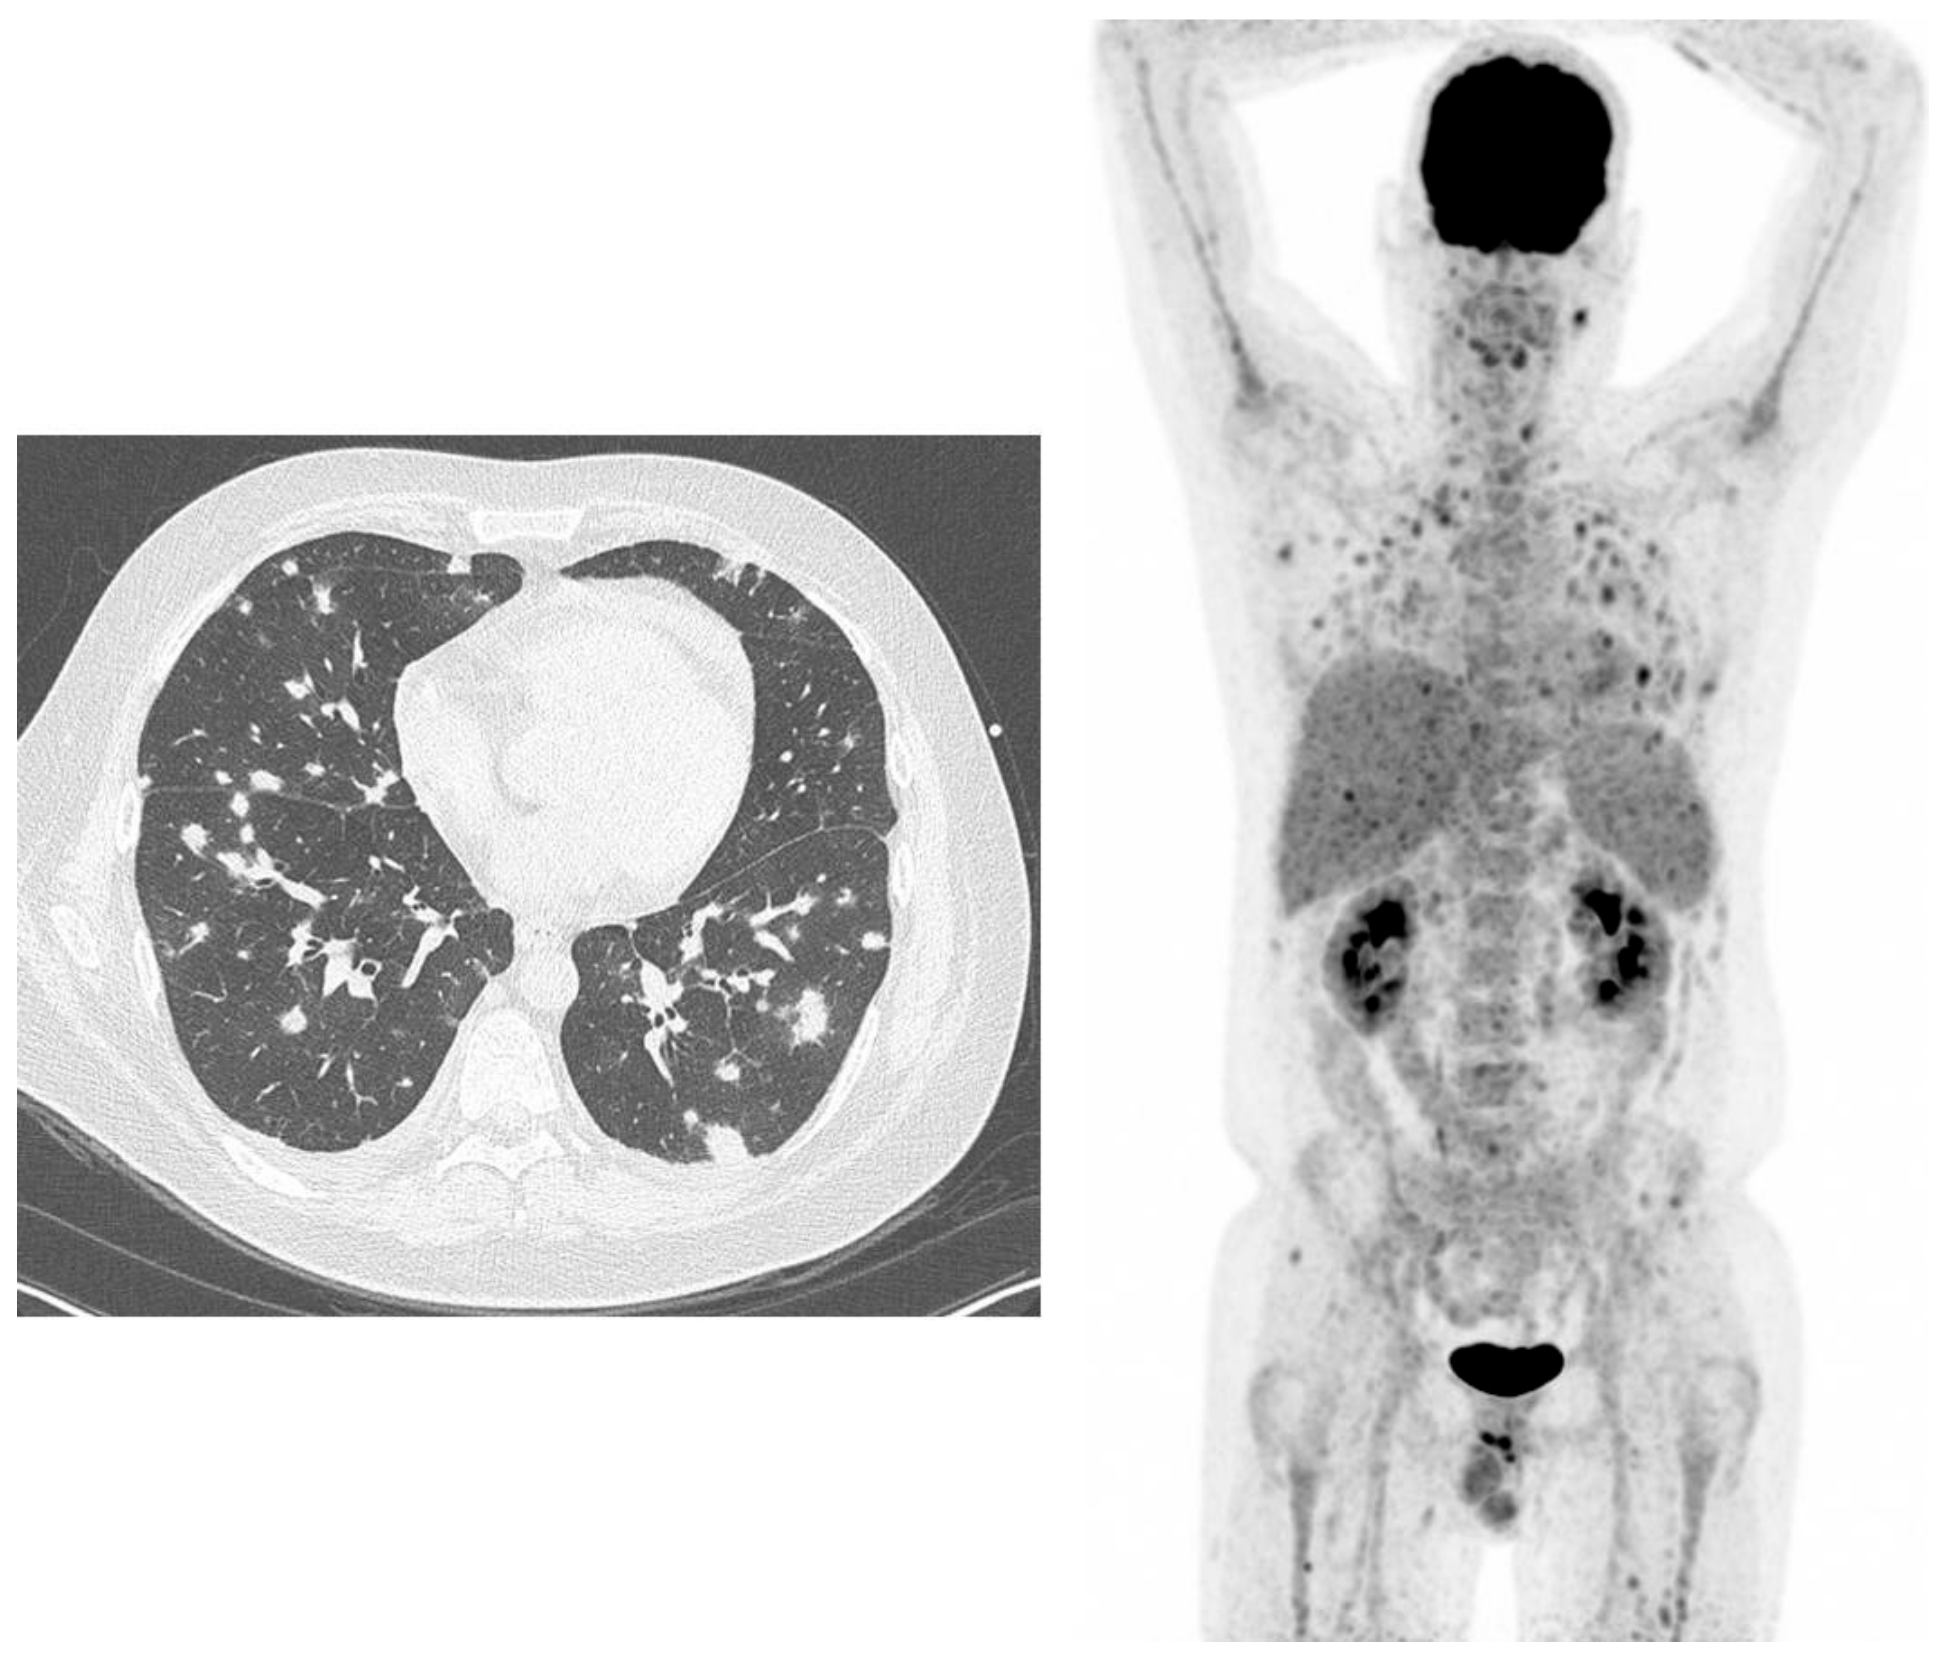

- Douglas, A.P.; Thursky, K.A.; Worth, L.J.; Drummond, E.; Hogg, A.; Hicks, R.J.; Slavin, M.A. FDG PET/CT imaging in detecting and guiding management of invasive fungal infections: A retrospective comparison to conventional CT imaging. Eur. J. Nucl. Med. Mol. Imaging 2019, 46, 166–173. [Google Scholar] [CrossRef] [PubMed]

- Leroy-Freschini, B.; Treglia, G.; Argemi, X.; Bund, C.; Kessler, R.; Herbrecht, R.; Imperiale, A. 18F-FDG PET/CT for invasive fungal infection in immunocompromised patients. QJM Int. J. Med. 2018, 111, 613–622. [Google Scholar] [CrossRef]

- Ankrah, O.A.; Span, L.F.R.; Klein, H.C.; de Jong, P.A.; Dierckx, R.A.J.O.; Kwee, T.C.; Sathekge, M.M.; Glaudemans, A.W.J.M. Role of FDG PET/CT in monitoring treatment response in patients with invasive fungal infections. Eur. J. Nucl. Med. Mol. Imaging 2019, 46, 174–183. [Google Scholar] [CrossRef]